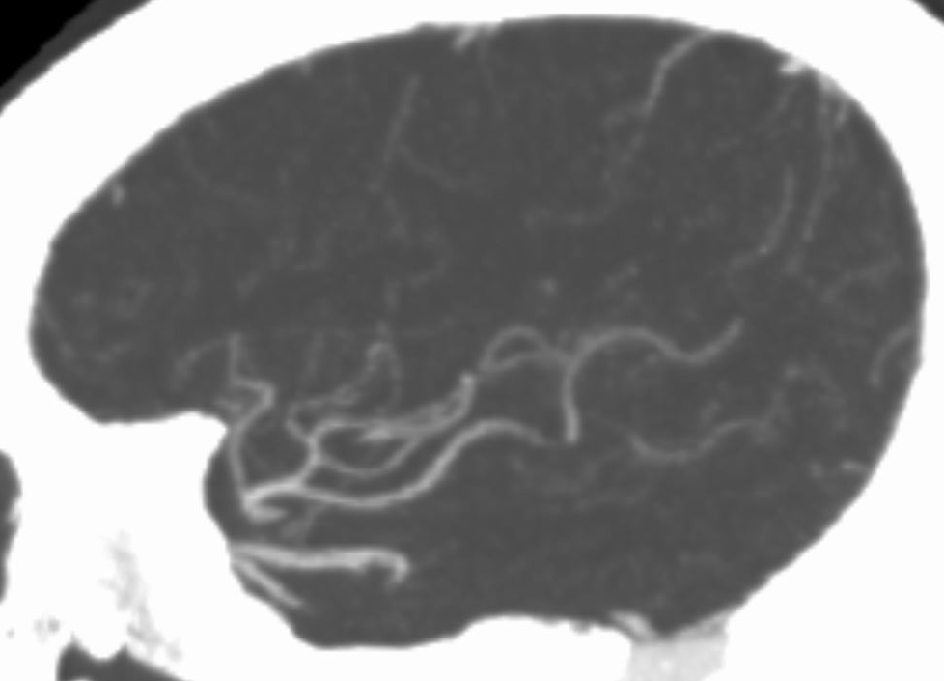

术前CTA:

CTA提示右侧大脑中动脉闭塞,左侧A1纤细。